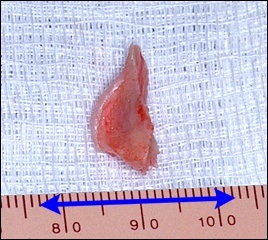

A fotó távoli nazális gerinc. On line távolság centiméterben, és a fekete nyíl képviseli a távolság egy inch.

A jobb felső sarokban a kép jól látható acanthion (sárga színnel jelöltek). Az alsó képen az azonos, de a távoli nazális gerinc.

A hossza a kék nyíl egyenlő egy hüvelyk.